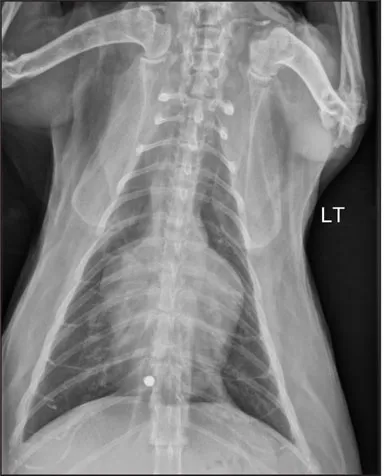

CASE 1.4 A 13-year-old spayed female mixed breed dog with a history of polyuria and polydipsia and abdominal distension. You obtain these thoracic radiographs: Fig. 1.4a, left lateral projection; Fig. 1.4b, dorsoventral projection.

1 What are your radiographic findings?

2 What is your radiographic diagnosis?

3 Are any additional radiographs needed?

Image

1.4a

1.4b